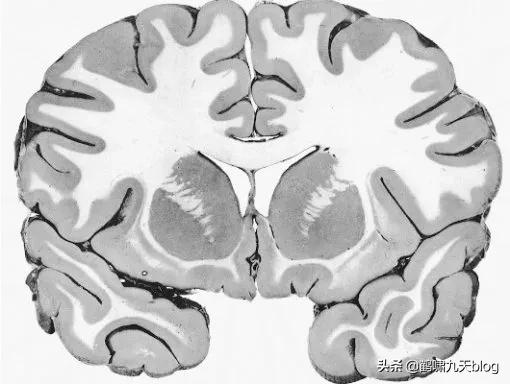

我们先通过一个脑半球切片来看一下大脑的几个主要部分:

我们把大脑从头部取出,然后移除左半球,然后我们就能好好看看内部了。